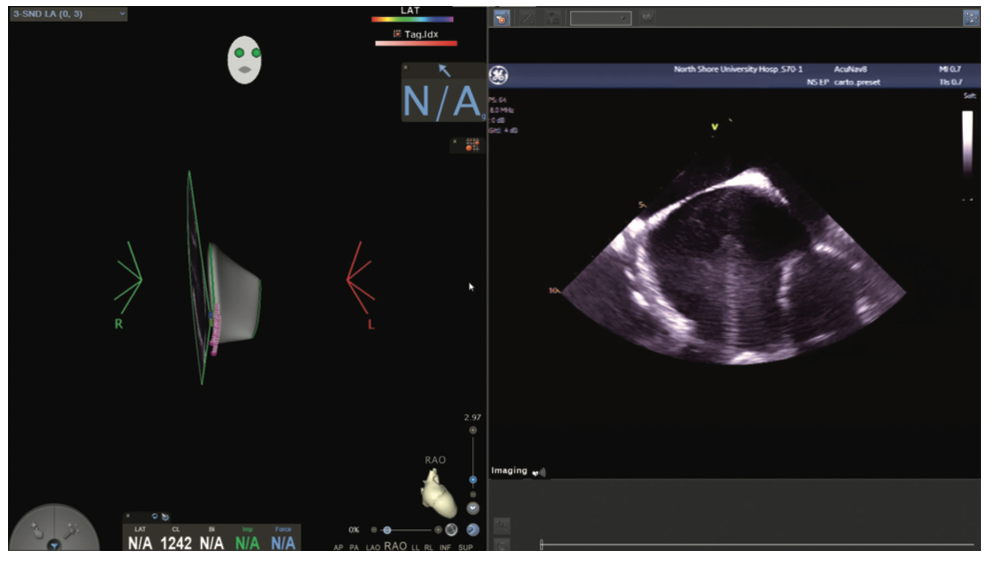

Figures/Videos 1-10 demonstrate the process of navigation from groin access to the heart to create biatrial geometry, localize the esophagus, and gain transseptal access. Many currently practicing electrophysiologists use very little fluoroscopy to map and ablate the left atrium (LA) with the current multielectrode catheters and EAM systems once transseptal access is obtained.